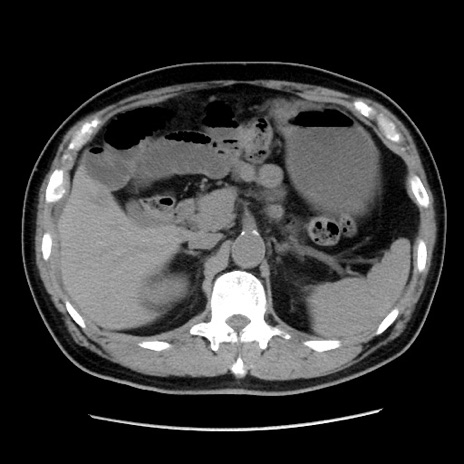

症例16(横断像)

【症例】 70歳代男性

【主訴】 腹痛、嘔吐

【現病歴】 約1ヶ月前より間欠的に腹痛と嘔吐あり、当院消化器内科を受診したところCTで多発する肝臓のLDAを指摘され、精査中であった。以降は消化器症状は安定していたが、2日前より嘔気と腹痛があり、同日より排便・排ガスが消失した。改善認めず、 本日、救急外来を受診した。

【既往歴】 大腸ポリープ切除後。

【身体所見】意識清明・会話良好、BT 36.3℃、BP 127/80mmHg、 P 80bpm、腹部:膨満あり、平坦・軟、上腹部正中および下腹部正中に圧痛あり、反跳痛なし、筋性防御なし。

【データ】WBC 7200、CRP 0.77